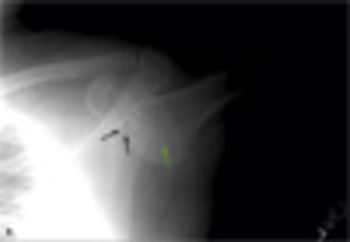

A firm mass projected from the deltoid muscle region of a 24-year-old man's right shoulder.

While jogging in a park, a 45-year-old man tripped and fell on his outstretched hand. As he fell, he tried to catch himself on a nearby park bench but was unsuccessful. He felt that his shoulder was out of place, and he was unable to adduct his arm from its erect position. A witness called for an ambulance, and the man was taken to the emergency department.